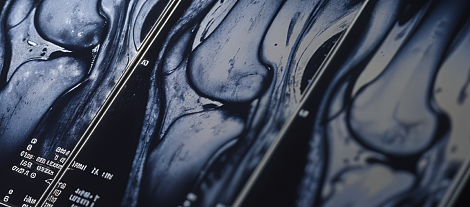

Поговорим о наших пациентах, которых мы видим каждый день на приеме? Обсудим, почему цели терапии иногда не достигаются? Как определить пациентов с высоким риском ишемических событий и какую терапию выбрать?

Пациенты, которые перенесли ОКС, нуждаются в приеме антиагрегантов в течение 12 месяцев после индексного события. Однако, есть и пациенты, которым требуется продление двойной антиагрегантной терапии. Важной частью терапии является контроль ХС ЛНП – неотъемлемый компонент как первичной, так и вторичной профилактики с помощью статинотерапии.